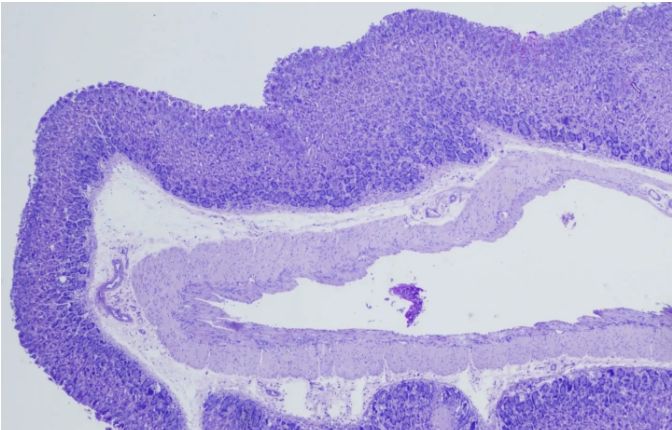

PAS染色實(shí)驗(yàn)過(guò)程中常見(jiàn)問(wèn)題解答由普拉特澤生物為大家總結(jié)分享。PAS染色作為一種在組織學(xué)中廣泛應(yīng)用的染色技術(shù),雖然具有高度的特異性和敏感性,但在實(shí)際操作過(guò)程中,也常會(huì)遇到一些問(wèn)題和挑戰(zhàn)。本文是關(guān)于PAS染色實(shí)驗(yàn)的最后一篇介紹,前面我們學(xué)習(xí)了PAS染色實(shí)驗(yàn)材料有哪些?、PAS染色和mpo染色區(qū)別是什么?、PAS染色實(shí)驗(yàn)注意事項(xiàng)以及PAS染色臨床應(yīng)用,可以點(diǎn)擊標(biāo)題直接傳送回去學(xué)習(xí)的哦。普拉特澤生物組織染色檢測(cè)平臺(tái)承接酵母雙雜實(shí)驗(yàn)外包上百例,早就為大家把實(shí)驗(yàn)過(guò)程中要踩的雷、吃的虧幫大家吃完了,現(xiàn)在我們就來(lái)看看,PAS染色中常見(jiàn)問(wèn)題的解答:

綜上所述,PAS染色雖然是一種常用的組織學(xué)染色方法,但在實(shí)際操作中常常會(huì)遇到一些問(wèn)題。通過(guò)掌握常見(jiàn)問(wèn)題及其解決方法,我們可以更好地應(yīng)用這項(xiàng)技術(shù),提高染色效果和觀察結(jié)果的準(zhǔn)確性。同時(shí),不斷學(xué)習(xí)和實(shí)踐也是提高PAS染色技術(shù)水平的重要途徑。